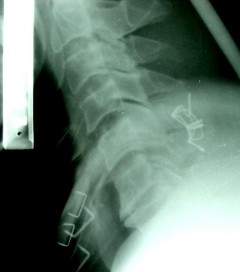

SAU MỔ: C5-C6 đã được nắn chỉnh. KHX Bohlman cải tiến.

THẲNG NGHIÊNG

SAU MỔ 4 THÁNG: tình trạng KHX vẫn tốt, không di lệch thứ phát, không giãn chỉ, không đứt chỉ.